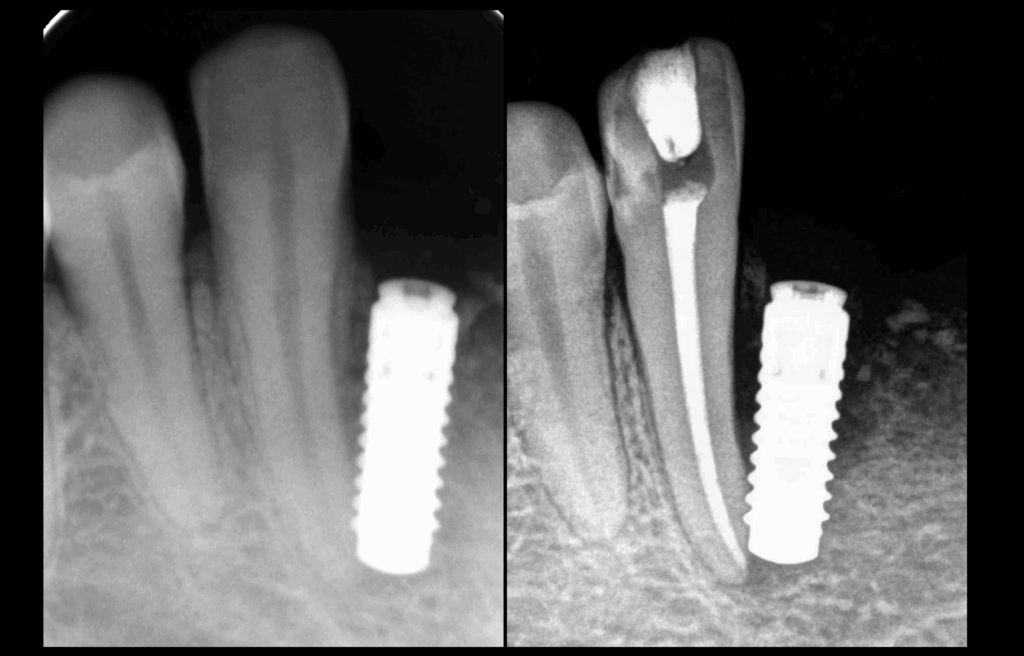

🦷 𝐐𝐮𝐚𝐧𝐝 𝐥’𝐢𝐦𝐩𝐥𝐚𝐧𝐭𝐨𝐥𝐨𝐠𝐢𝐞 𝐚 𝐮𝐧 𝐢𝐦𝐩𝐚𝐜𝐭 𝐞𝐧𝐝𝐨𝐝𝐨𝐧𝐭𝐢𝐪𝐮𝐞.

🚨 𝐏𝐮𝐥𝐩𝐢𝐭𝐞 𝐚𝐢𝐠𝐮ë 𝐢𝐫𝐫𝐞́𝐯𝐞𝐫𝐬𝐢𝐛𝐥𝐞 𝐭𝐫𝐚𝐢𝐭𝐞́𝐞 𝐞𝐧 𝐮𝐫𝐠𝐞𝐧𝐜𝐞 𝐩𝐚𝐫 𝐭𝐫𝐚𝐢𝐭𝐞𝐦𝐞𝐧𝐭 𝐜𝐚𝐧𝐚𝐥𝐚𝐢𝐫𝐞.